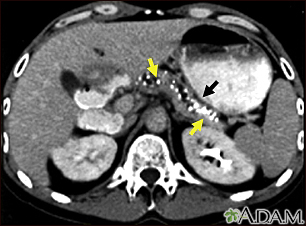

Pancreatitis, chronic - CT scan